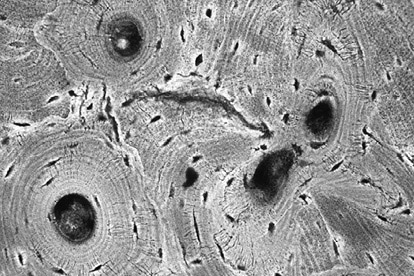

Иллюстрация к книге — Кости: внутри и снаружи [i_016.jpg]

Под микроскопом видно, что компактная костная ткань состоит из множества цилиндров, диаметр которых примерно в три раза больше толщины человеческого волоса. Эти цилиндры образованы концентрическими слоями кости вокруг центрального канала. Через каждый центральный канал проходят кровеносные сосуды, которые снабжают питательными веществами окружающие канал клетки (маленькие черные точки на фото)

Shutterstock.com